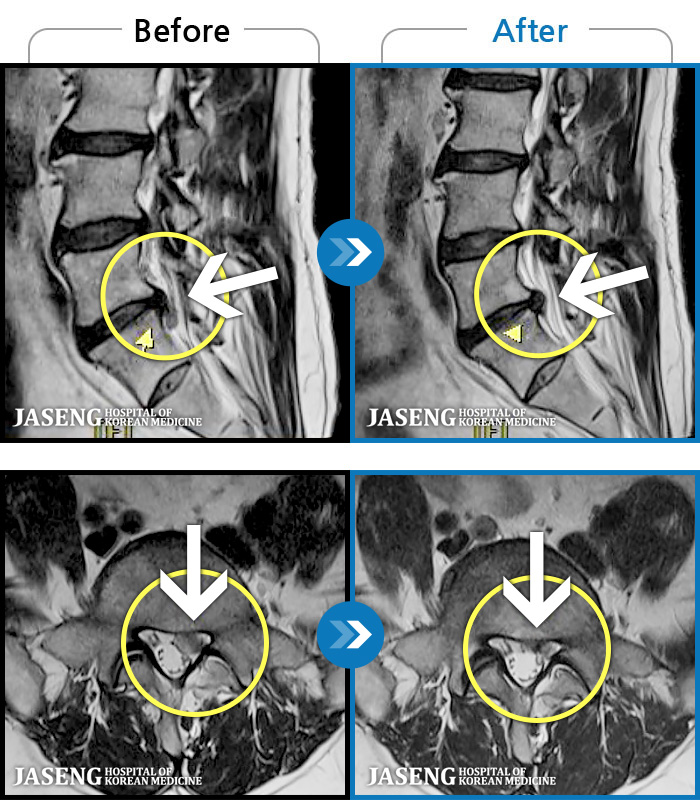

허리디스크

광주 · 김동은 원장

양측 허리부터 양측 골반까지 당기는 통증, 양측 하지 후면으로 이어지는 통증

촬영시기

2022.09.05 ~ 2024.05.06

2024.05.24

조회수 451